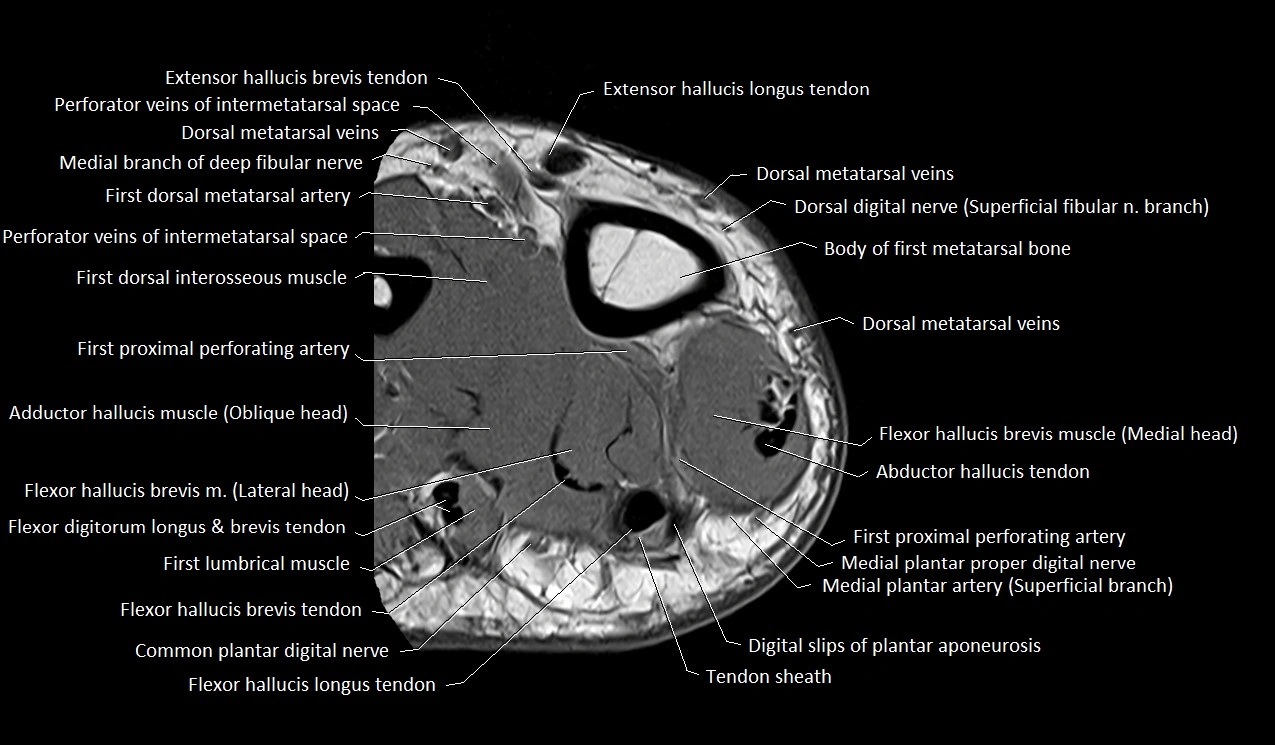

MRI image

image